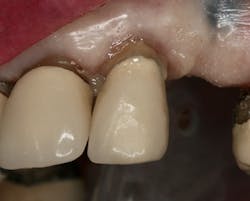

Figure 13: Crown seat resin-bonding together the two segments (root and crown)

FuturabondUadhesive was applied and cured. The intaglio surface of the crown was filled with Rebilda DC cement, which was also used to “buttercoat” the root surface and cut the post bundle. The two segments were then joined and resin-bonded together by using a curing light and waiting the manufacturer-specified time for the dual-cure polymerization reaction to complete (figure 13). The excess cement was removed and the margins checked for any gaps.

The existing partial was then tried in to verify proper relation to rest seats and guide planes (figure 14).